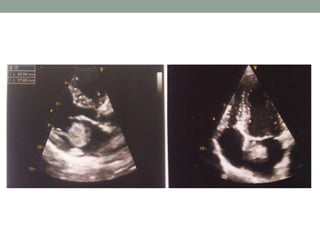

Ecocardiograma: “Cavidades cardíacas de dimensões normais; (…) VE

com boa e uniforme contractilidade; Sem sinais de envolvimento

orgânico. AE com estrutura ecodensa, móvel (21*27mm) pediculada ao

SIA, compatível com Mixoma”